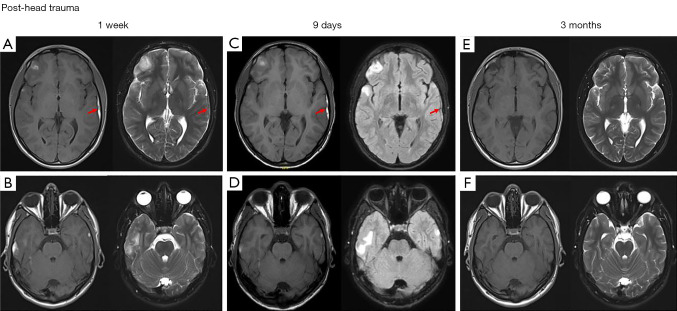

Case description: A previously healthy 19-year-old man presented with symptoms of intracranial hypertension and back pain with radiculopathy without focal neurologic deficits. Craniospinal magnetic resonance imaging (MRI) detected bilateral CSDHs, cerebral contusions, and lumbosacral, anterior SSDH simultaneously, 1 week after isolated head trauma and unremarkable cranial computed tomography (CT). A positive "inverted Mercedes-Benz sign" in axial T1 and T2 sequences confirmed the diagnosis. We report the first case of contemporaneously diagnosed SSDH and CSDH with cerebral contusions following head trauma without spinal trauma, whereby all pathologies were managed conservatively. Furthermore, we performed a review of pertinent literature available in PubMed. Twelve cases with contemporaneous diagnosis of CSDH and SSDH within a narrow diagnostic timeframe of ≤48 hours were published since 2005. All but one was male with a mean age of 41.5 years (range, 11-70 years). Fifty percent reported cranial trauma. Nine cases (66.7%) had headaches, and 10 patients (83.3%) reported radiculopathy. Nine patients (66.7%) reported cranial and spinal symptoms. All 5 patients (41.7%) treated conservatively for both pathologies showed complete clinical and radiological resolution at follow-up.